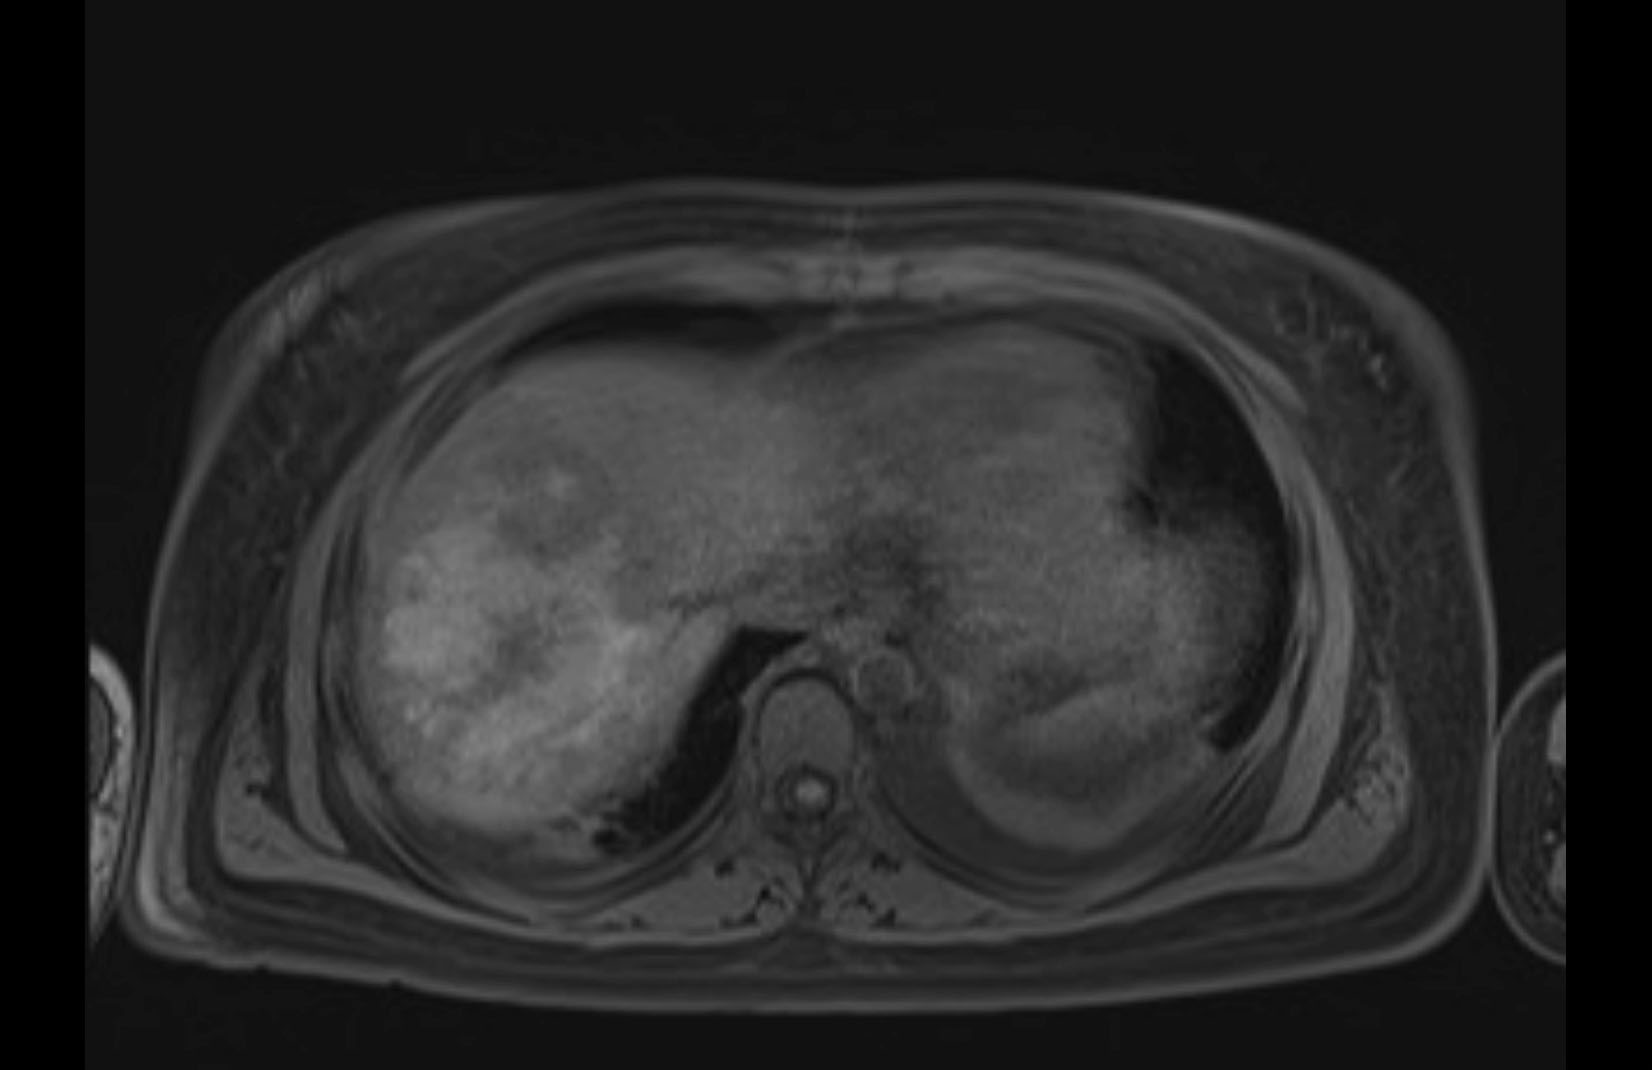

MRI T1

MRI T2